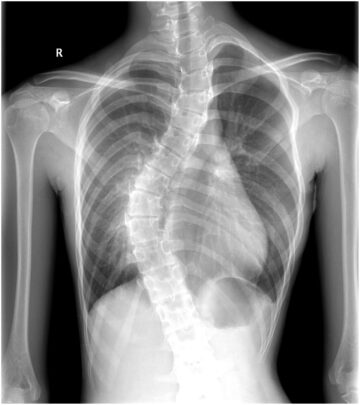

تأثير اعوجاج العمود الفقري على القفص الصدري والرئة عند المراهقين: هل يسبب ضيق تنفس؟ يُعتبر اعوجاج العمود الفقري مجهول السبب عند المراهقين (Adolescent Idiopathic Scoliosis – AIS) من أكثر التشوهات الشائعة التي تصيب العمود

تأثير اعوجاج العمود الفقري على الرئة والتنفس عند الأطفال والمراهقين اعوجاج العمود الفقري، أو ما يُعرف طبيًا بـ”الجنف”، هو حالة شائعة تؤدي إلى انحناء غير طبيعي في العمود الفقري. ورغم أن الكثير من الناس